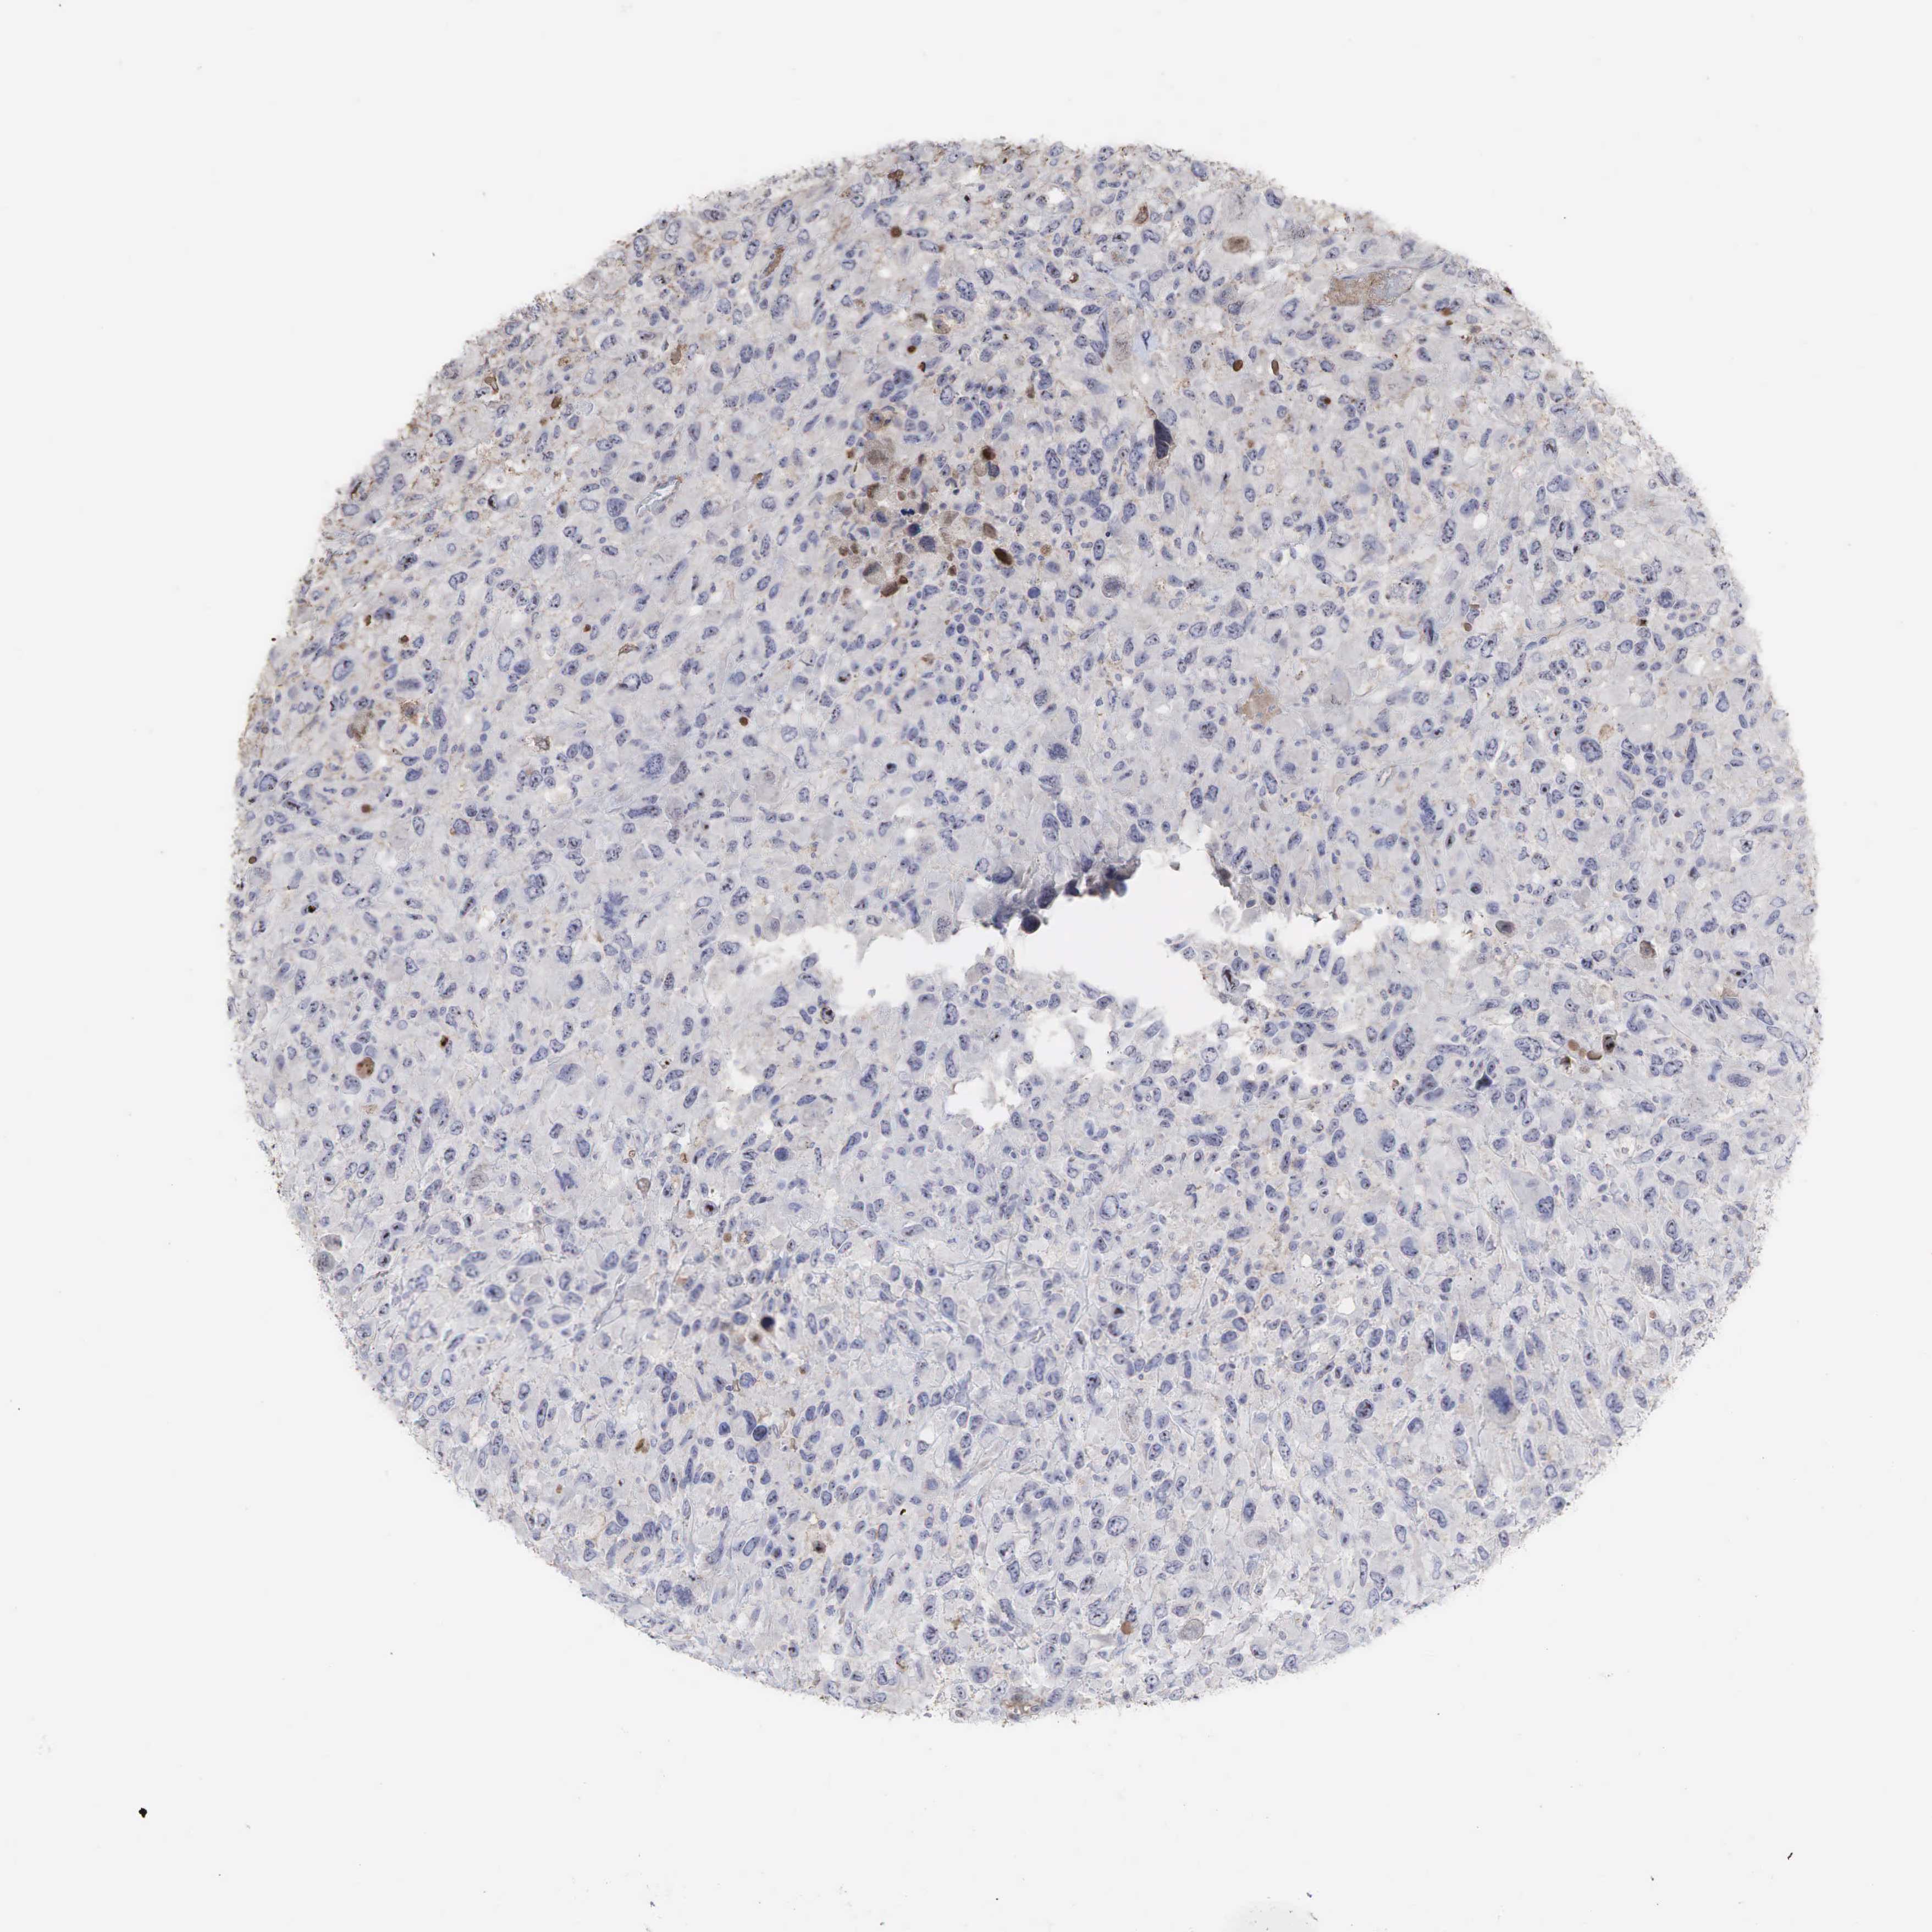

KIDNEY RENAL CLEAR CELL CARCINOMA (TCGA) - Interactive survival scatter ploti

The Survival Scatter plot shows the clinical status (i.e. dead or alive) for all individuals in the patient cohort, based on the same data that underlies the corresponding Kaplan-Meier plots. Patients that are alive at last time for follow-up are shown in blue and patients who have died during the study are shown in red.

The x-axis shows the expression levels (FPKM) of the investigated gene in the tumor tissue at the time of diagnosis. The y-axis shows the follow-up time after diagnosis (years). Both axes are complimented with kernel density curves demonstrating the data density over the axes. The top density plot shows the expression levels (FPKM) distribution among dead (red) and alive patients (blue). The right density plot shows the data density of the survived years of dead patients with high and low expression levels respectively, stratified using the cutoff indicated by the vertical dashed line through the Survival Scatter plot. This cutoff is automatically defined based on the FPKM cutoff that minimizes the p-score. The cutoff can be changed by dragging the vertical line or by entering a cutoff value in the square labeled "Current cut-off".

Under the Survival Scatter plot the p-score landscape (black curve; left axis) is shown together with dead median separation (red curve; right axis). Dead median separation is the difference in median mRNA expression between patients who have died with high and low expression, respectively. It is calculated as follows: median FPKM expression of dead patients with high expression - median FPKM expression of dead patients with low expression. This is intended to aid the user in visually exploring custom cutoffs and the associated p-scores and dead median separation.

Individual patient data is displayed and can be filtered by clicking on one or more of the category buttons on the top of the page. Categories describing expression level and patient information include: high, low, alive, dead, female, male and tumor stages. The scale of the x-axis can be toggled between linear and log-scale by clicking on the "x log" button. Mouse-over function shows TCGA ID, patient information and mRNA expression (FPKM) for each patient.

& Survival analysisi

Kaplan-Meier plots summarize results from analysis of correlation between mRNA expression level and patient survival. Patients were divided based on level of expression into one of the two groups "low" (under cut off) or "high" (over cut off). X-axis shows time for survival (years) and y-axis shows the probability of survival, where 1.0 corresponds to 100 percent.

DKC1 is potential prognostic, high expression is favorable in Kidney Renal Clear Cell Carcinoma (TCGA)

Best expression cut offi

Based on the FPKM value of each gene, patients were classified into two groups and association between prognosis (survival) and gene expression (FPKM) was examined. The best expression cut-off refers the FPKM value that yields maximal difference with regard to survival between the two groups at the lowest log-rank P-value. Best expression cut-off was selected based on survival analysis .

When clicking on this number, the vertical dashed line indicating cut-off, the interactive survival plot, and the Kaplan-Meier curve will be adjusted to show results based on the best expression cut-off.

: 19.53

TCGA RNA samplesi

RNA-seq data is reported as average FPKM (number Fragments Per Kilobase of exon per Million reads), generated by the The Cancer Genome Atlas (TCGA) .

Normal distribution across the dataset is visualized with box plots, shown as median and 25th and 75th percentiles. Points are displayed as outliers if they are above or below 1.5 times the interquartile range. FPKM values of the individual samples are presented next to the box plot.

Average pTPM 22.3

Number of samples 521